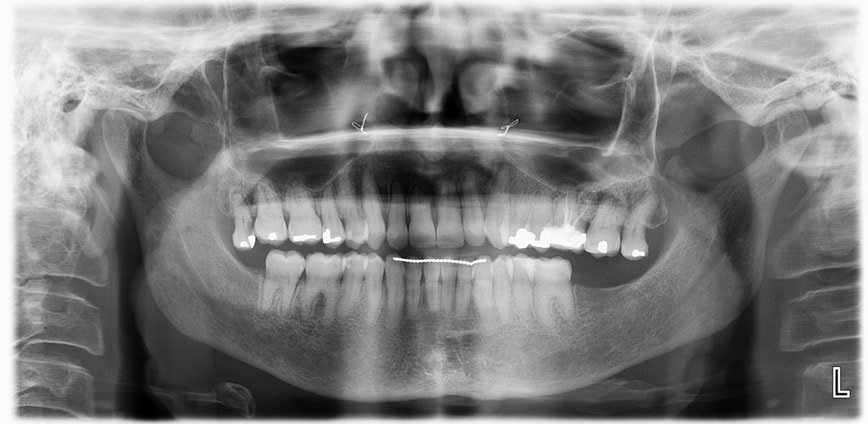

The final cephalometric analysis and the structural superimpositions show an incredible anterior mandibular auto-rotation with a counter clockwise movement of the face, the mandibular plane and the occlusal plane leading to a skeletal and bite closure.

Within the sagittal skeletal patterns, the slight proclination of the incisors after treatment helped to get an ideal overjet/overbite and an improvement of the profile. (Table 4-2)

The 3D scanner confirms a rapid and total transverse bone mending, a large increase of the pharyngeal airways’ volume, guarantee of stability with an horizontalization of the occlusal plane. (Table 4-3)

The patient was referred to a general dentist to extract 18 /28 and to the prosthodontist to replace 37 with an implant, to do ceramic rehabilitation and gingivoplasty involving a muccogingival procedure which should give the patient a significant and delicate final touch.